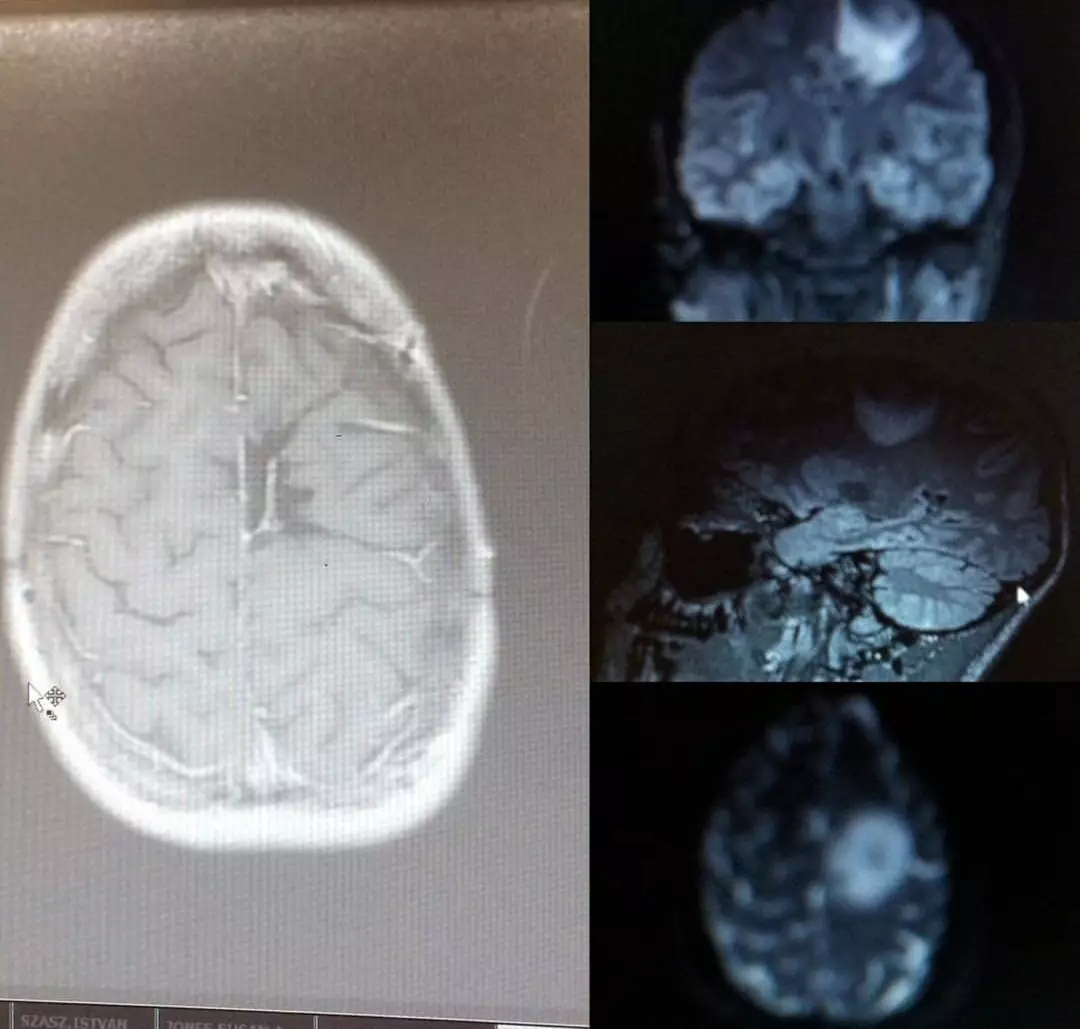

A história de Amy começou em 2015, quando ela desmaiou ao ver uma aranha em seu quarto. Na época, os médicos atribuíram o episódio a uma simples fobia, mas a situação se mostrou muito mais grave quando ela sofreu outros dois desmaios durante treinos na academia. Exames revelaram a presença de um tumor do tamanho de uma bola de golfe. Amy passou por cirurgia, quimioterapia e radioterapia para removê-lo, e durante anos acreditou que estava livre da doença.

Amy descobriu que tinha um tumor do tamanho de uma bola de golfe crescendo em seu cérebro depois que os médicos inicialmente atribuíram os sintomas à aracnofobia (SWNS)